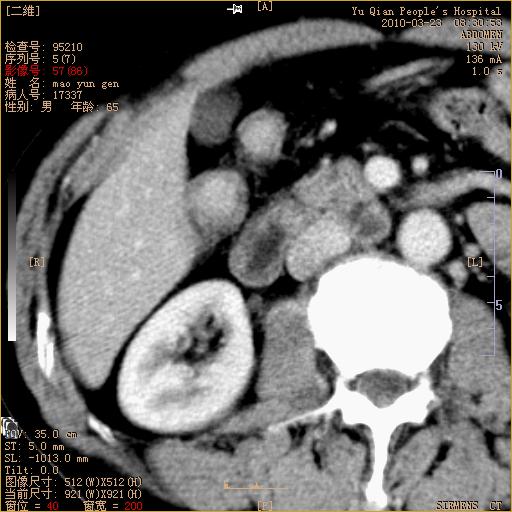

标题: CT25266:消瘦月余,前来肝部检查,请看看肠腔 [打印本页]

标题: CT25266:消瘦月余,前来肝部检查,请看看肠腔

肝区结肠占位,腺癌可考虑,建议肠镜活检。

升结肠肠壁增厚,不均强化,考虑升结肠腺癌可能性,建议肠镜检查。

1)考虑升结肠癌。2)右肾小囊肿。